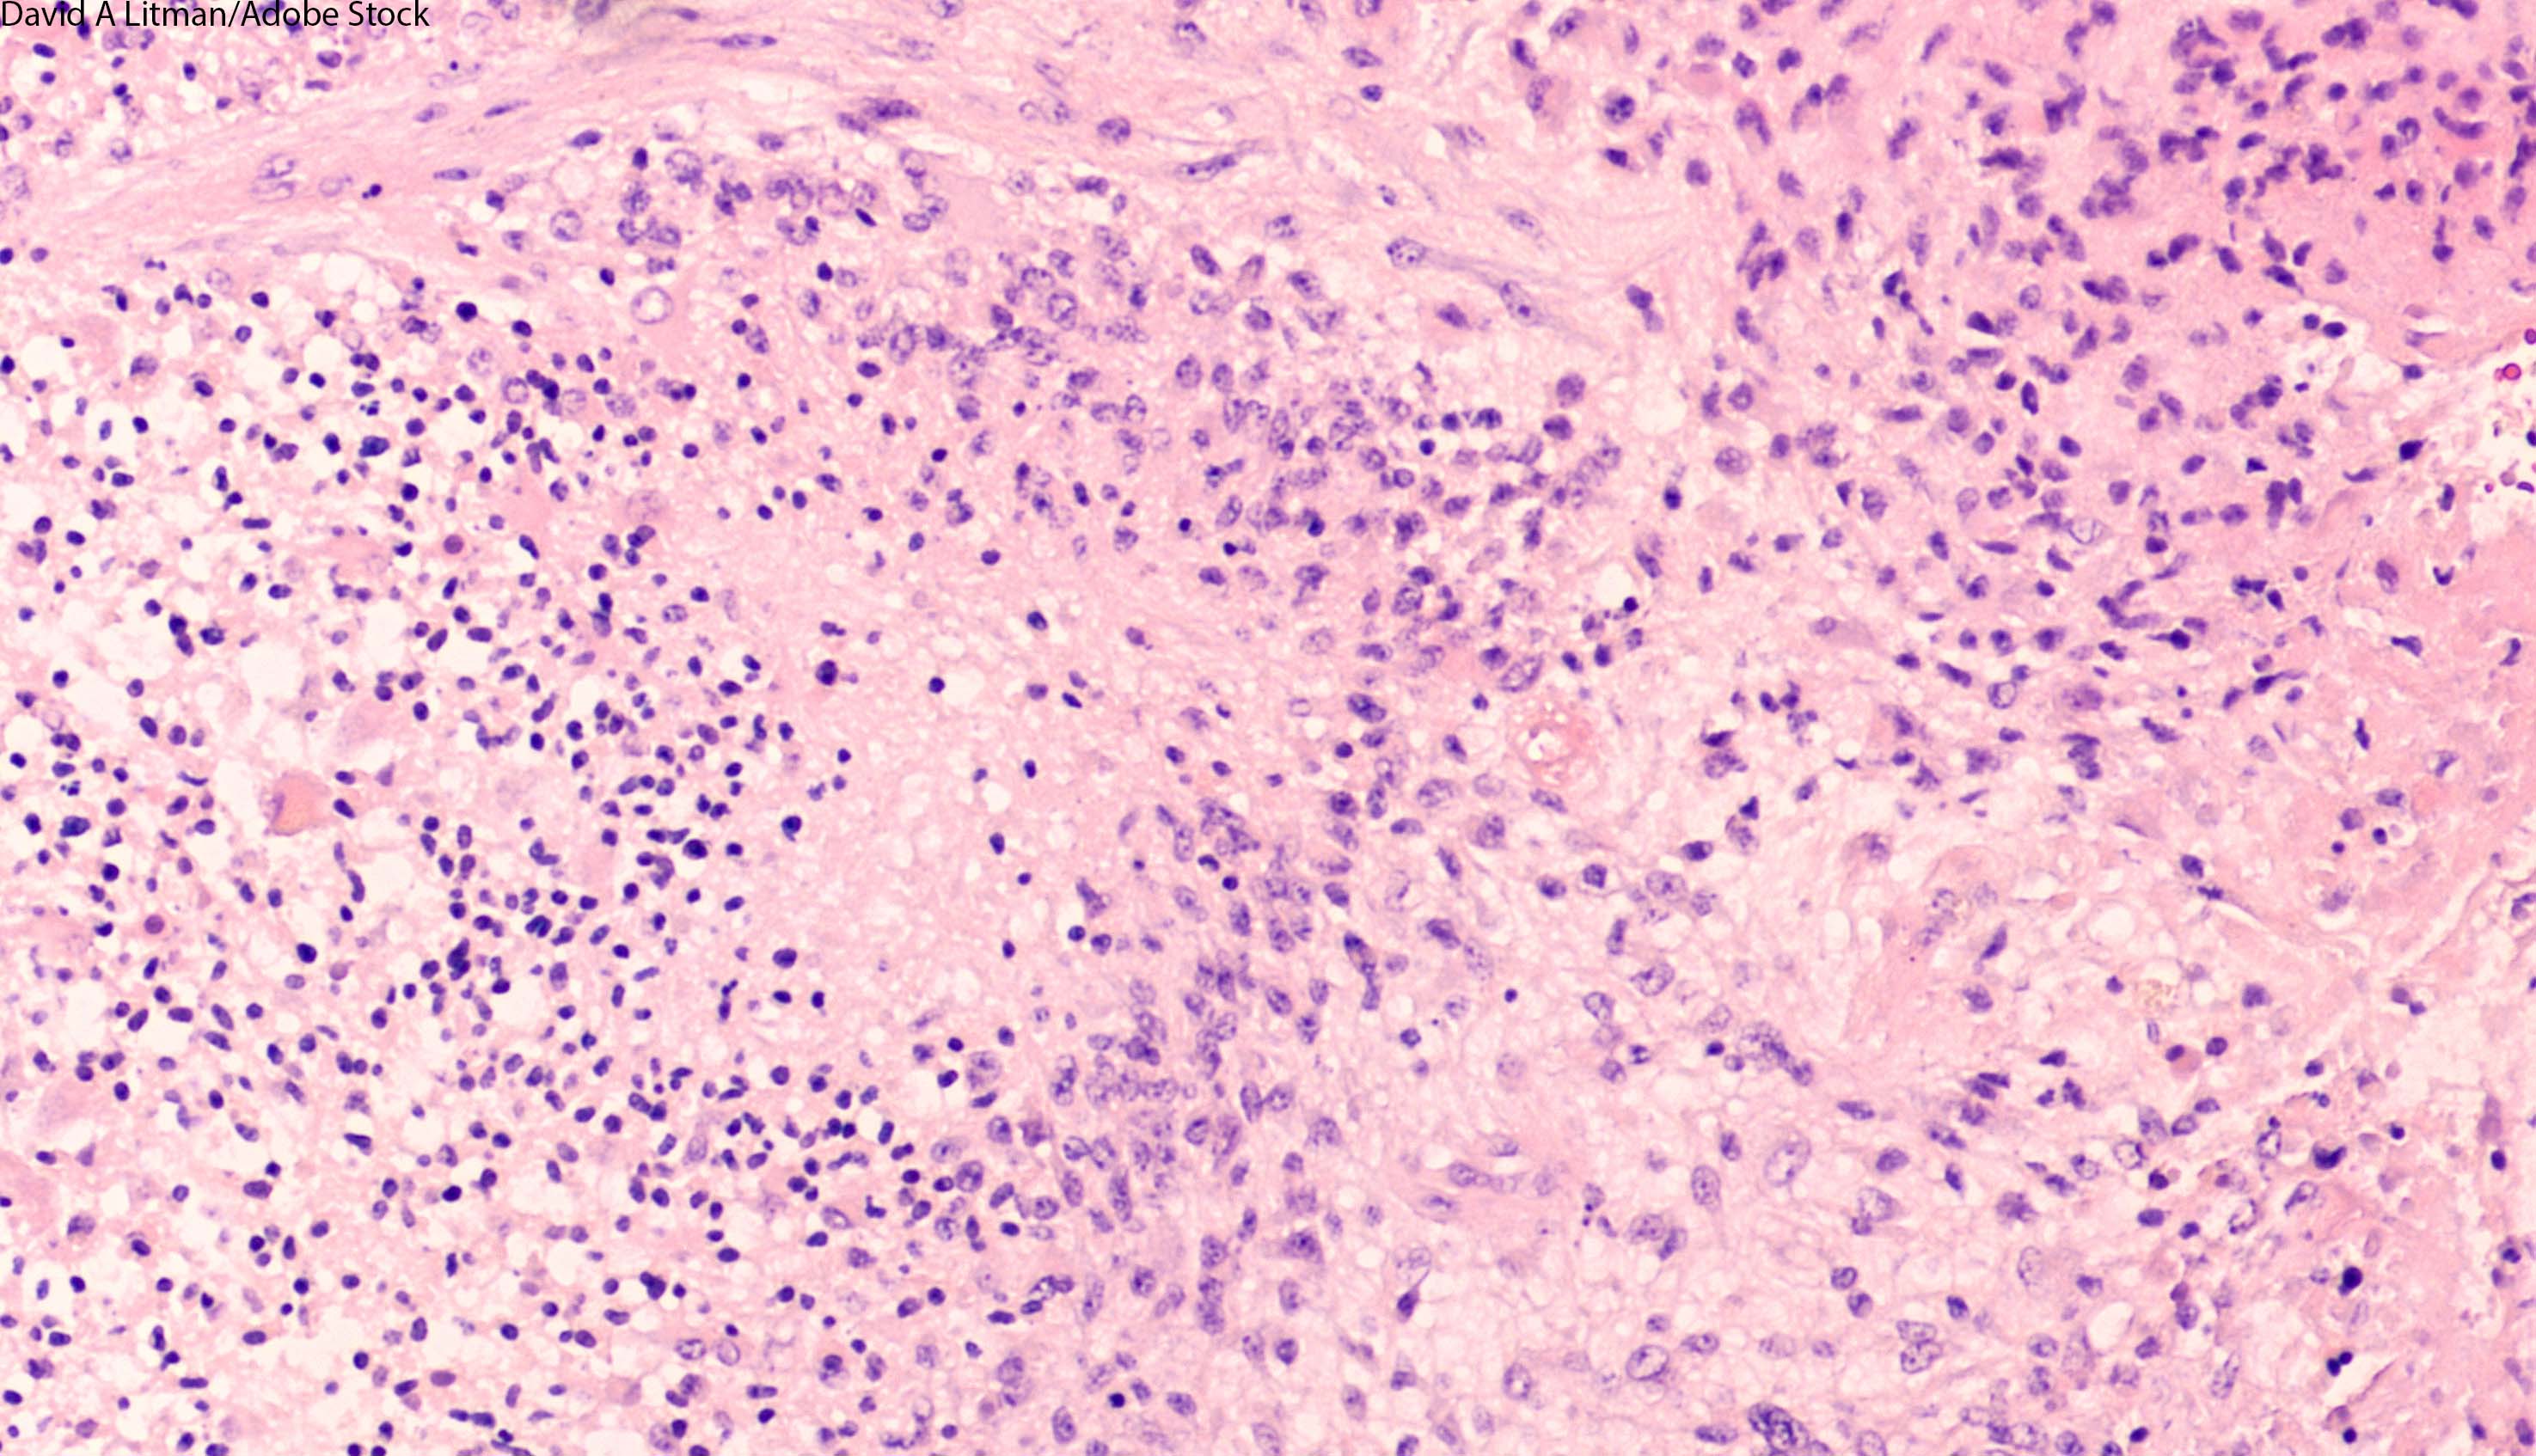

This review focuses on clinical developments and management of newly diagnosed glioblastoma, and includes a discussion about the incorporation of molecular features into the classification of this disease.

Here, in Part 1, we will provide an overview of the epidemiology of primary CNS lymphoma, followed by a discussion of the diagnostic and staging evaluation. We will also review the current prognostication systems for primary CNS lymphoma.